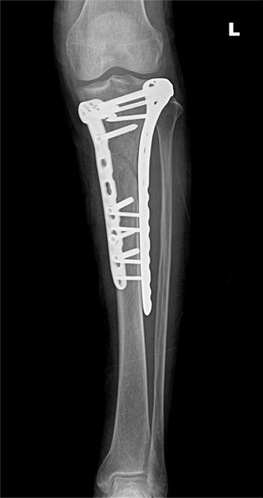

무릎관절 골절

무릎관절 골절의 치료

x-ray 사진

무릎골절